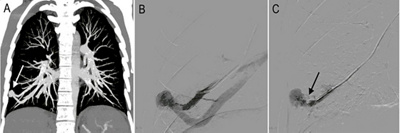

A: Computertomografie (CT) bei einem 55-jährigen Mann mit Morbus Rendu-Osler, der zuvor symptomatisch wurde durch einen zerebrovaskulären thrombembolischen Ereignis, deren neurologische Symptome sich komplett wieder zurückbildeten. B zeigt eine von insgesamt drei pulmonalen arteriovenösen Fisteln, welche allesamt mittels Gefässkorken (Vascular Plug) in einer Sitzung verschlossen werden konnten (C, Pfeil)

Pulmonale AVFs können sehr risikoarm interventionell mit mechanisch ablösbaren Embolisationsmaterialien verschlossen werden, welche eine hohe technische Sicherheit der Prozedur ermöglichen. Hierdurch ist der minimalinvasive Verschluss solcher Fisteln mittlerweile die Therapie der ersten Wahl geworden. Der Eingriff bedarf keiner Vollnarkose, kann also in Lokalanästhesie durchgeführt werden. Hierbei werden die Pulmonalgefässe mit einem feinen Katheter unter Röntgen-Durchleuchtung über die Leistenvene sondiert und die fistulöse Verbindungsstelle der AVF mittels Metallspiralen (Coils) oder Gefässkorken (Amplatzer Plug) verschlossen.

Leider werden Betroffene oftmals erst im Rahmen von Komplikationen auffällig. Deshalb ist bei Angehörigen von Patienten mit Morbus Rendu-Osler ein entsprechendes Screening von hoher Relevanz. Bei asymptomatischen Patienten beinhaltet die Indikation zur Therapie die Prävention von neurologischen Komplikationen und Lungenblutungen. Hierbei wird ein arterieller Durchmesser von mehr als 3 mm als Therapiekriterium angesehen. Zur Detektion, Indikationsstellung und Therapieplanung ist eine kontrastmittelgestützte Computertomografie (CT) die radiologische Bildgebung der Wahl.